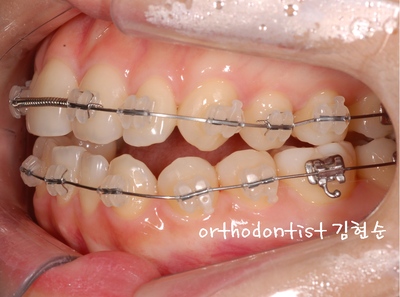

세라믹 치과 김현순 대표 원장님 -

개방 교합 -

교정 문의 환자 : 김 0 0

나이 : 24 세 F

교정 사유 : 앞니 / 치열 / 교합